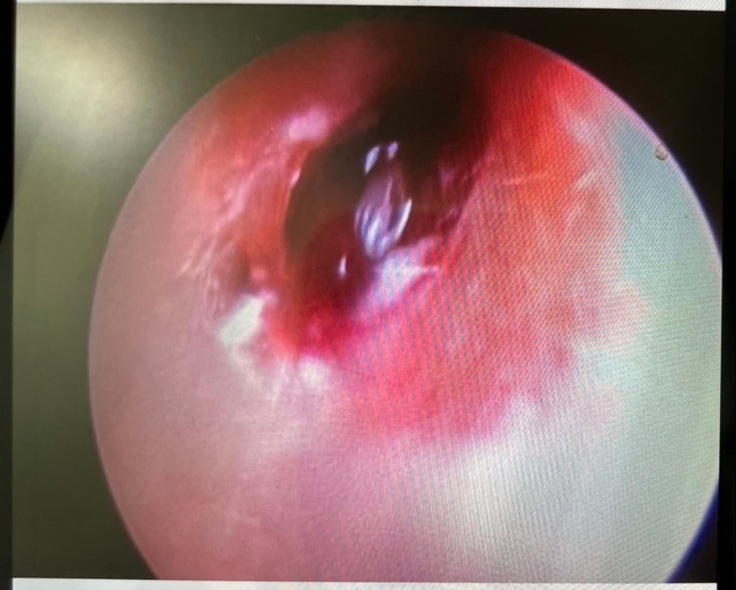

手術の結果としては外耳に腫瘍がありそちらを少しずつ取り除いていただきました。

一枚目は手術前、2枚目は切除あと。

こちらは切除していただいた腫瘍です。

ただ問題は鼓膜近くの見えている外耳の腫瘍ではなく、その先。つまり鼓膜の中、中耳の鼓室から腫瘍が派生していると思われるとのこと。

鼓膜を破っての腫瘍の派生とのこと。

幸いこの腫瘍は良性が多いということですが確認の為、病理検査に出すことになりました。

腫瘍が派生していると考えられる鼓室は汚れているのがCTで分かりました。

取り敢えずは外耳の腫瘍をとったことで状態がどうなるかを確認してみたいとのことです。